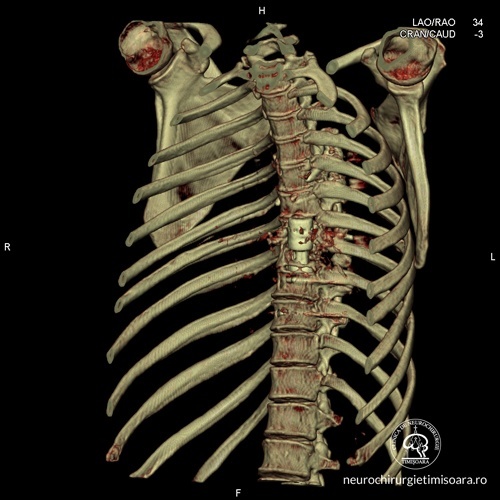

Patologia coloanei vertebrale